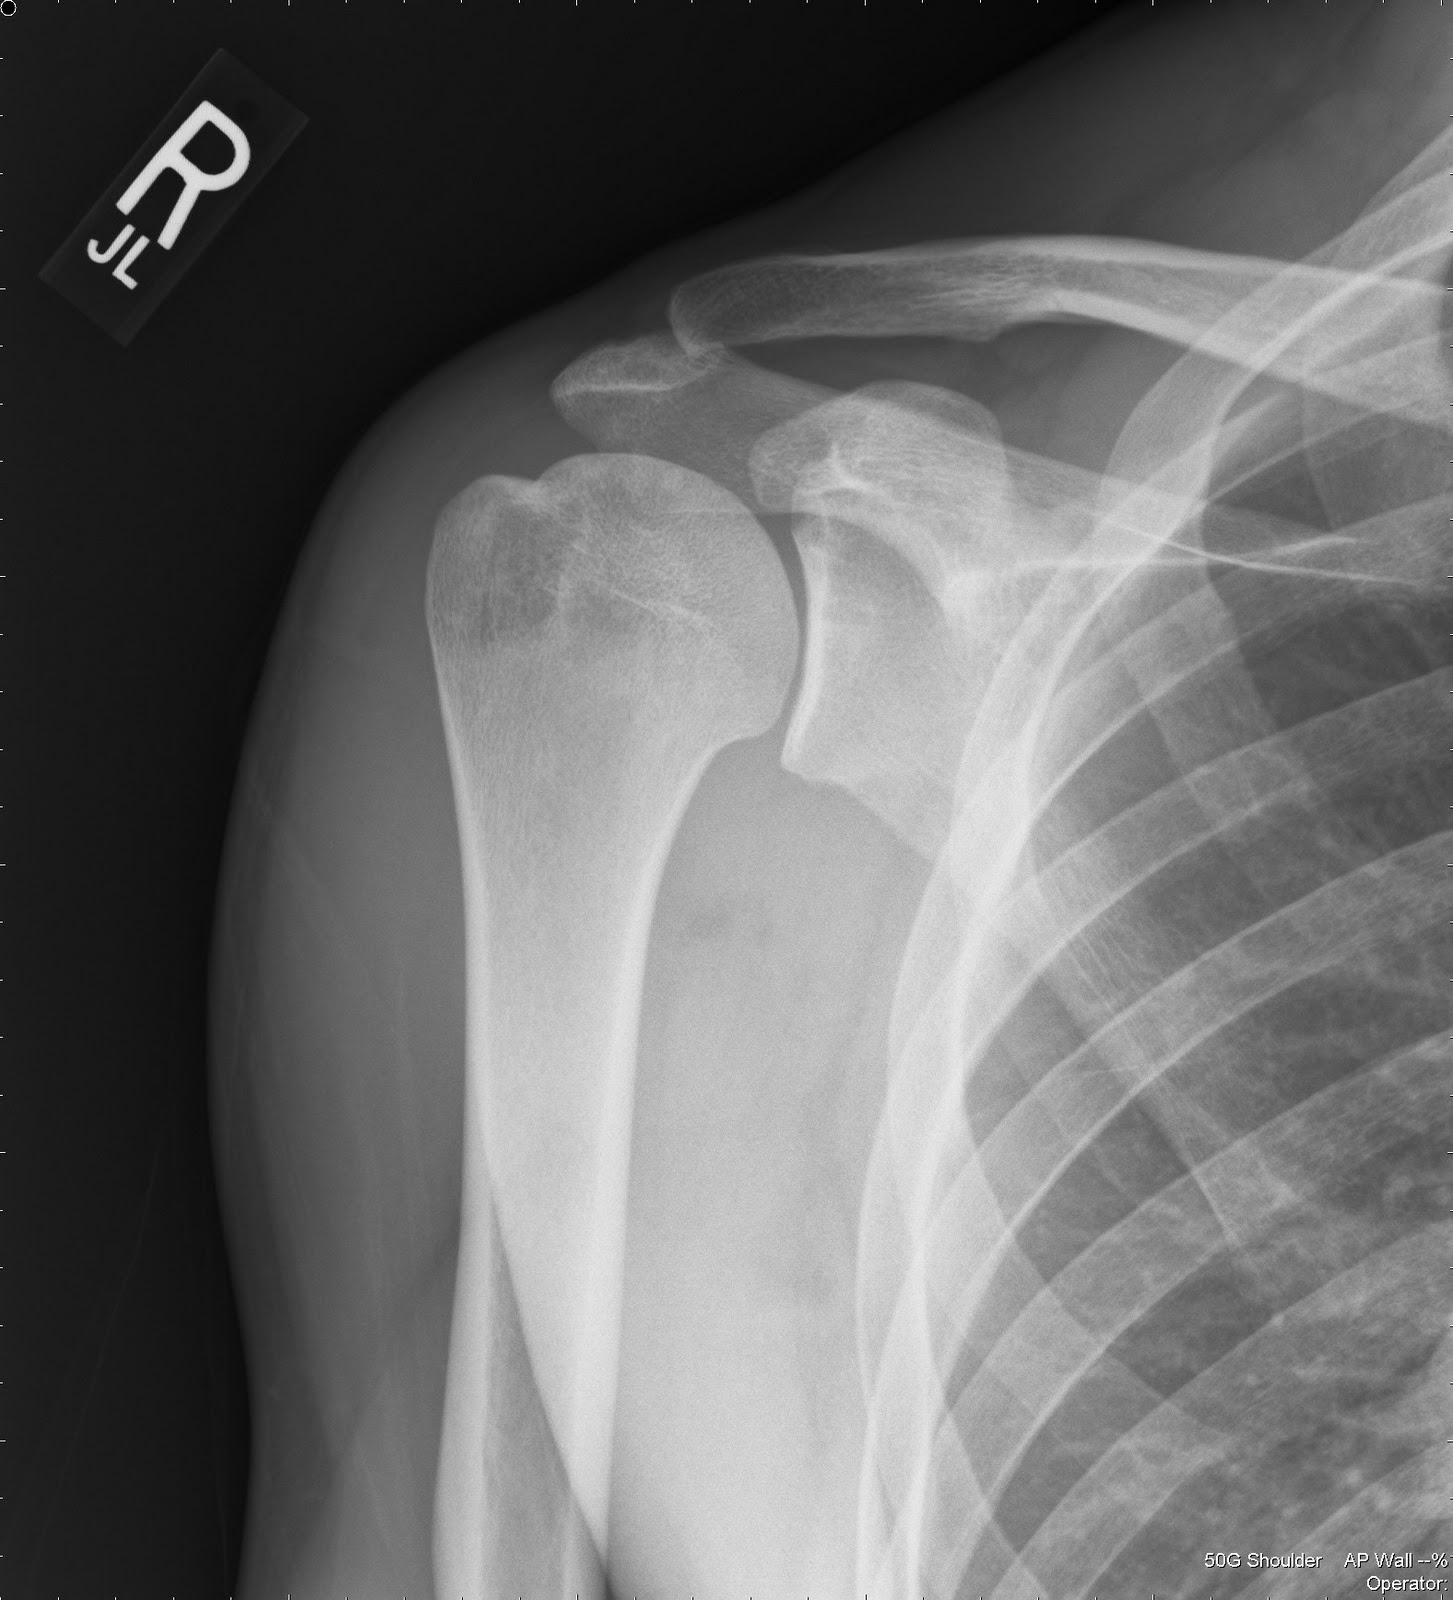

To understand Rotator Cuff Impingement, it is helpful to look at the anatomy of the shoulder. The rotator cuff is a group of four muscles and their associated tendons that act to stabilize the humerus (upper arm bone) within the shoulder socket. These tendons pass through a tight gap called the subacromial space, situated between the top of your arm bone and the acromion (the bony tip of your shoulder blade).

When this space becomes narrowed, the tendons—particularly the supraspinatus tendon—get pinched or compressed during arm movement. Over time, this constant rubbing leads to inflammation, swelling, and pain. If left untreated, the repetitive nature of the impingement can lead to more serious issues, such as a full-thickness rotator cuff tear or chronic bursitis.

Anatomy of the shoulder showing the rotator cuff and subacromial space

X-rays Identifies bone spurs or structural abnormalities.